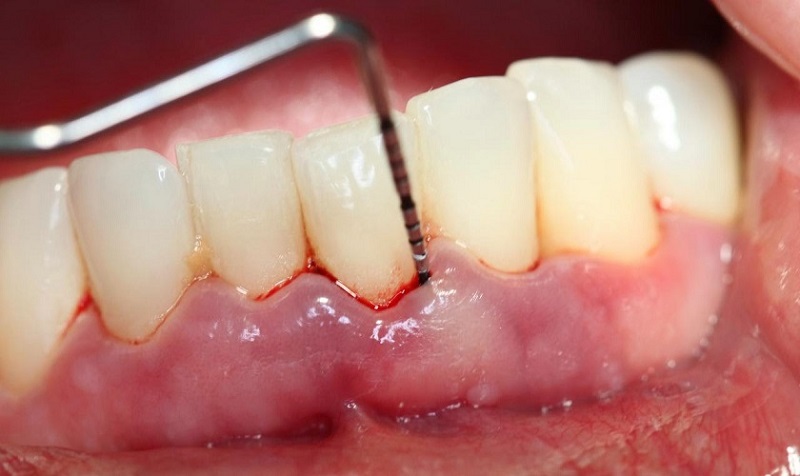

- Viêm nha chu mức độ nhẹ: Bác sĩ sẽ tiến hành loại bỏ mảng bám vi khuẩn, cạo vôi răng và làm sạch cao răng nhằm kiểm soát viêm nhiễm và ngăn bệnh tiến triển nặng hơn.

Khi Tùng Anh bị viêm nha chu có thể trồng răng được nếu đã điều trị và kiểm soát ổn định, nướu hết sưng đau, không còn chảy máu, vi khuẩn nha chu được loại bỏ và xương hàm đủ điều kiện nâng đỡ trụ răng.